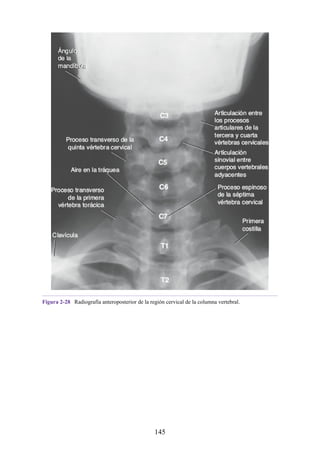

Notas clínicas

Lesiones ligamentosas